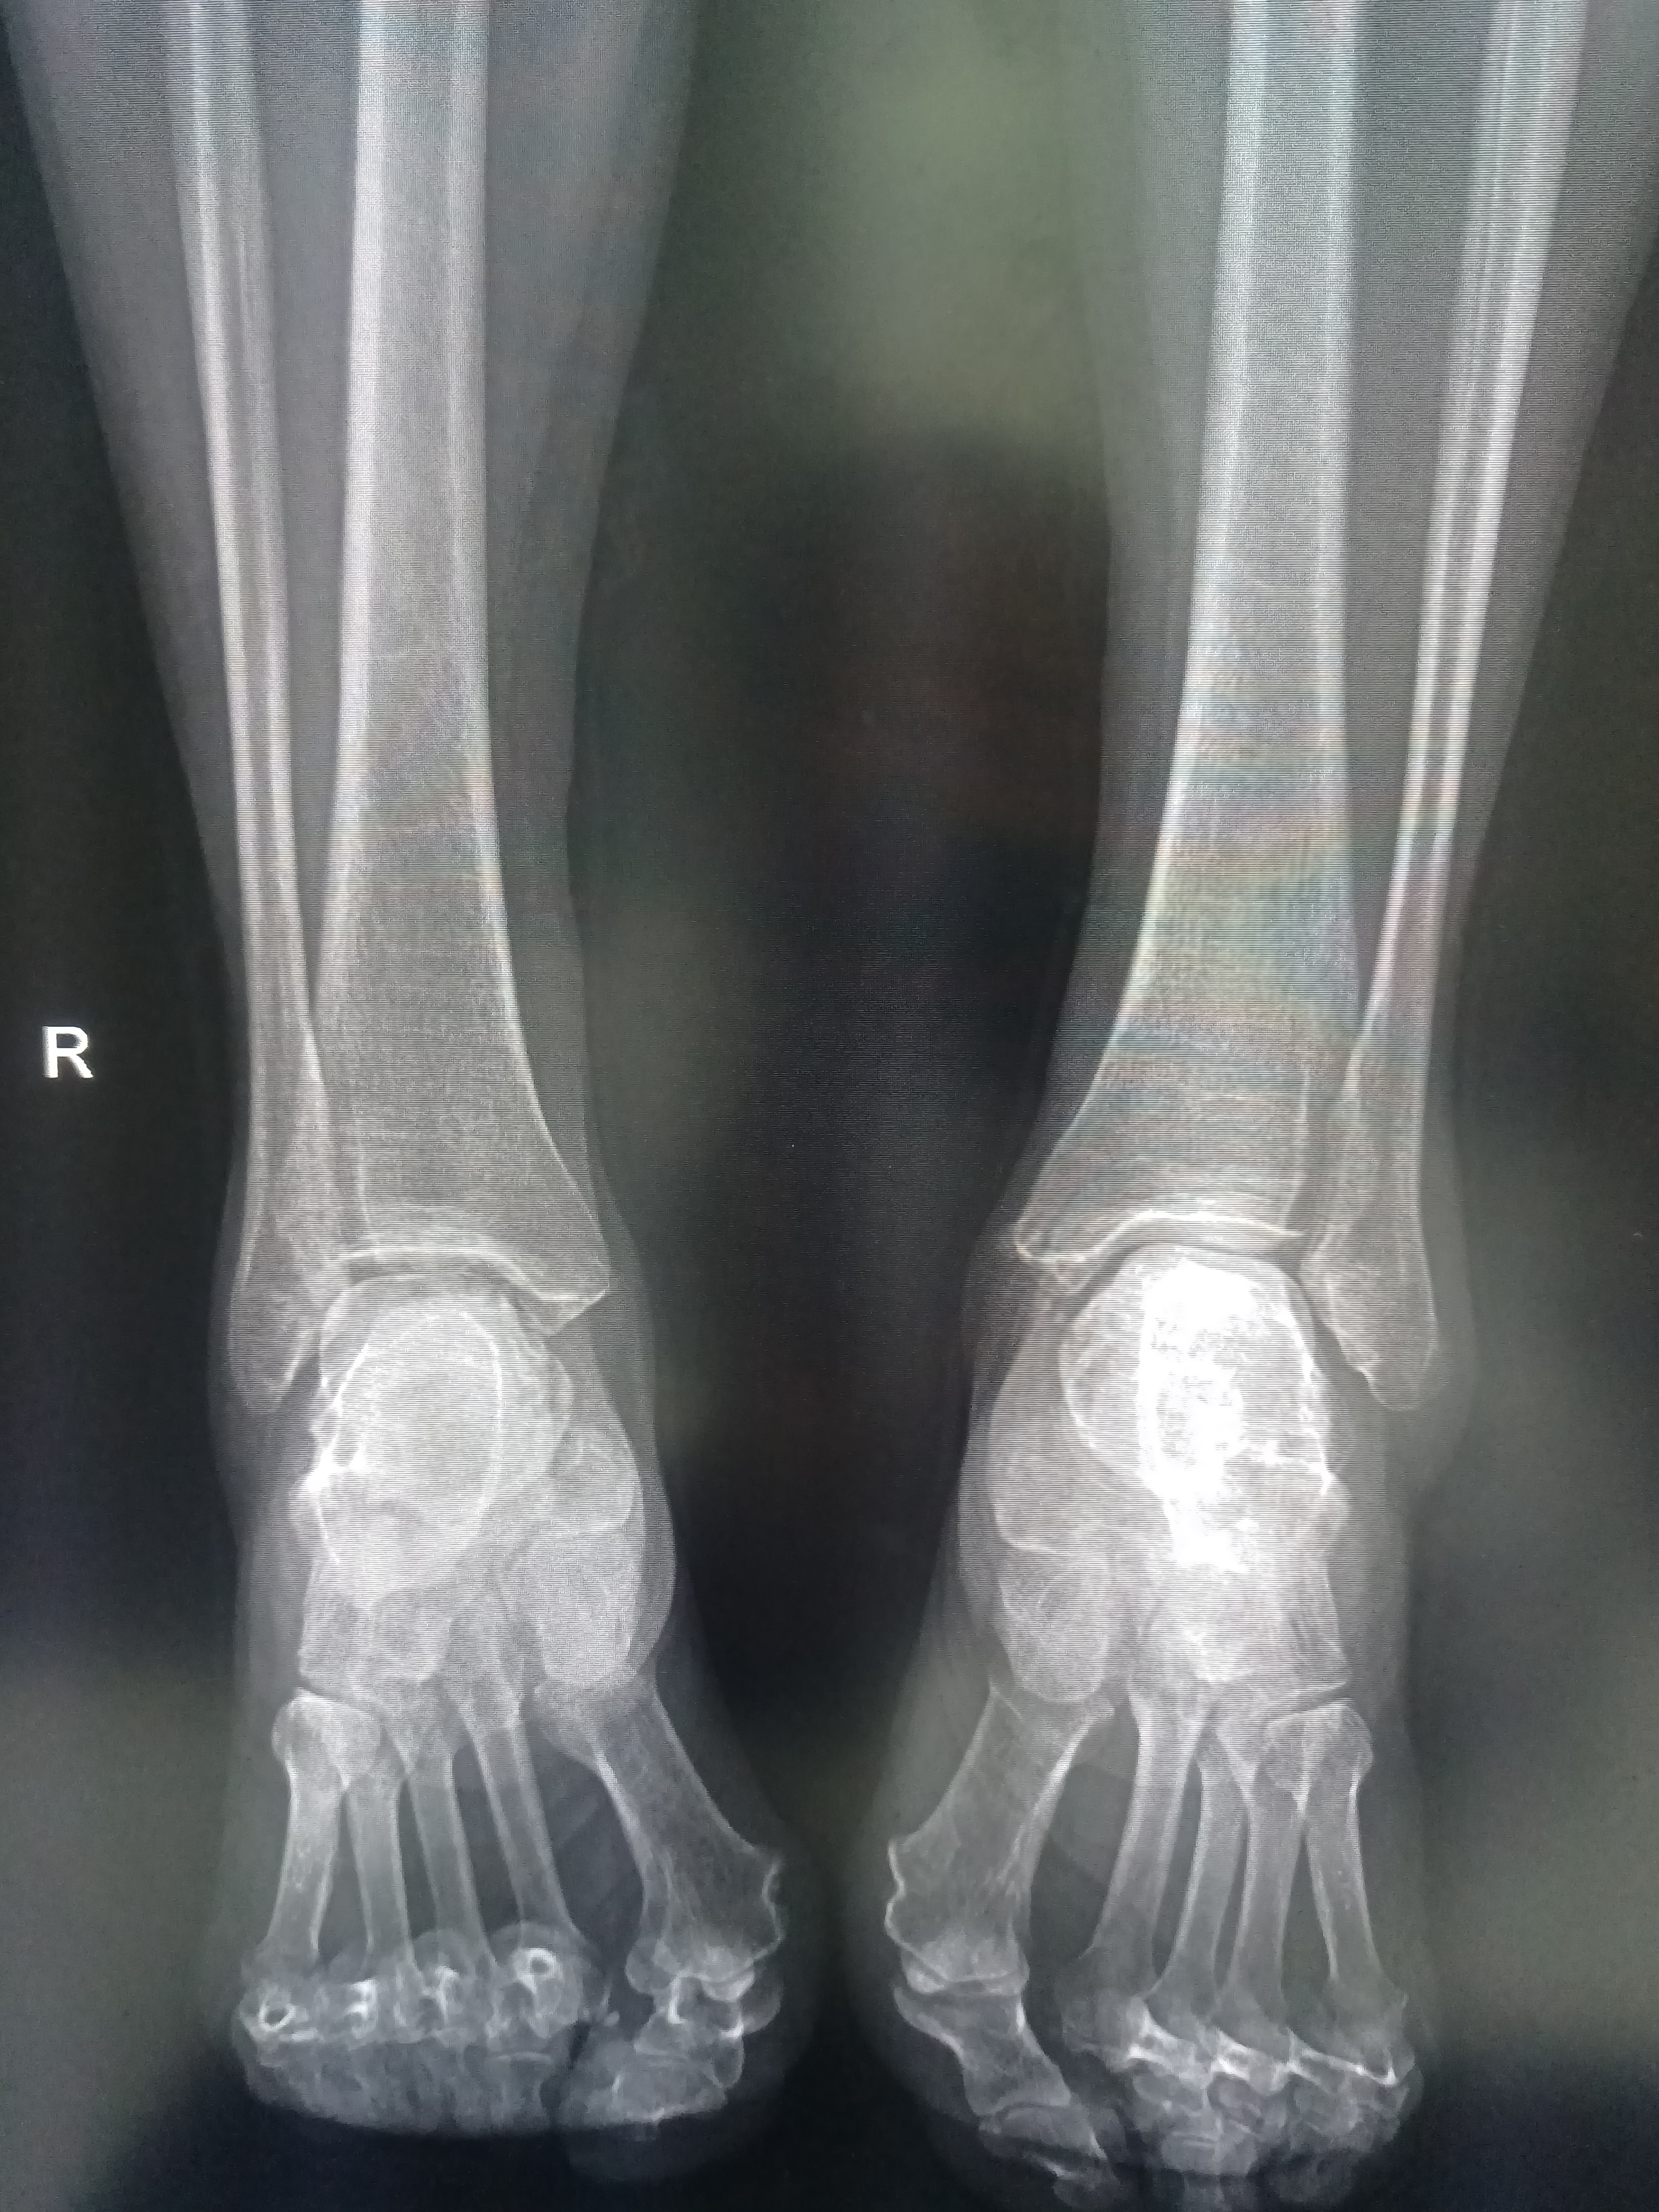

双足踝疼痛病例分享!